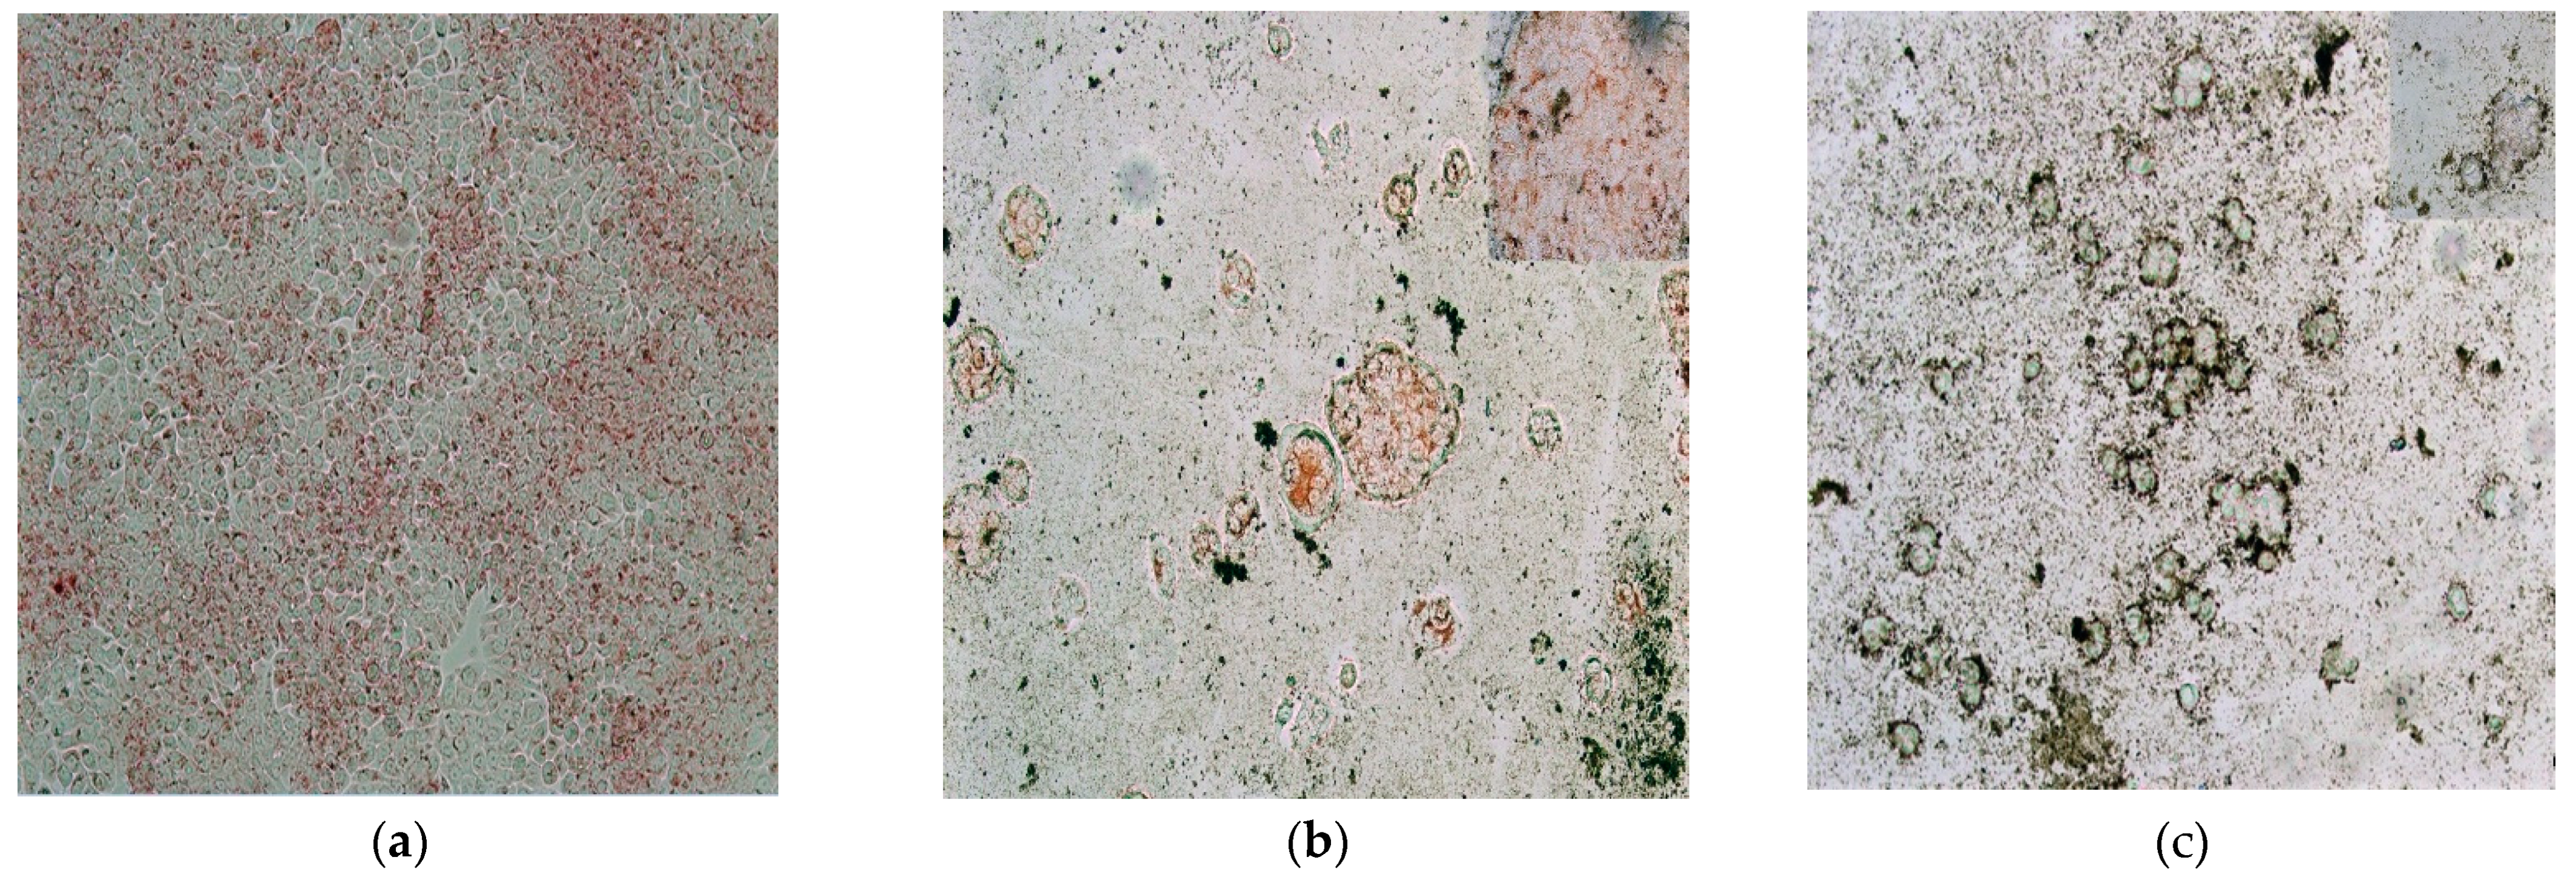

2. Results and Discussion

3.3. Oxidative Capability Analysis of the Catechol-Coated MNPs Ferrofluid

3.4. Cytotoxicity Analysis and Hyperthermia Assays of the Ferrofluid with CMNP